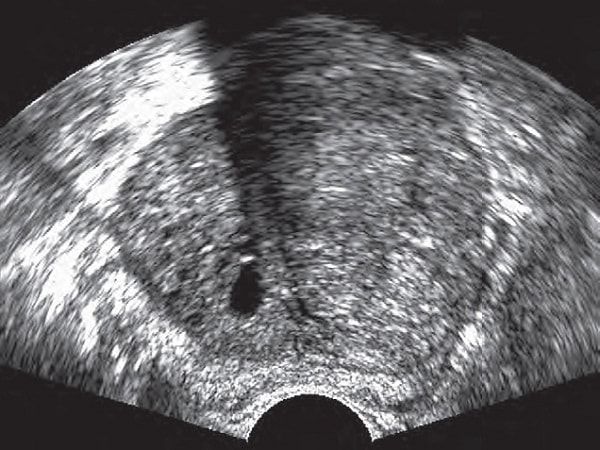

Siêu âm: Siêu âm sẽ cho hình ảnh đúng của bờ viền và của thể tích tuyến tiền liệt, cùng hình ảnh của các cơ quan lân cận như bàng quang, túi tinh. Phương pháp tin cậy này cho phép phát hiện ra ung thư nhỏ và hướng dẫn việc lấy sinh thiết.